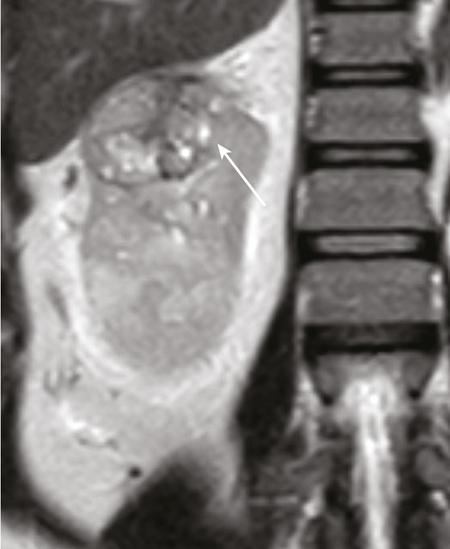

IMAGING OF RENAL MALIGNANCIES IN ADULTS Aparna Katdare, Palak Bhavesh Popat, Nilesh P. Sable, Ganesh Bakshi, Suyash Kulkarni Detection of renal masses has increased remarkably in recent times owing to wide-spread use of cross-sectional imaging. Imaging plays an important role in characterizing renal masses and is indispensable in treatment planning in renal malignancies. The most commonly encountered malignant renal masses in practice include renal cell carcinoma (RCC), urothelial carcinoma, lymphoma and metastases. Urothelial carcinoma and lymphoma have been covered in detail in separate chapters. RCC constitutes nearly 90% of all renal malignancies with a higher incidence in North America and Europe than India, Africa and China. With an increase in the number of cross-sectional studies performed, especially in Western population, the incidental diagnosis of RCC has increased in recent times, with such incidentally diagnosed lesions presenting at earlier stages with better prognosis and reduced rates of recurrence. The median age of presentation of RCC is 64 years according to the Surveillance, Epidemiology and End Results (SEER) program database and almost a decade earlier in Indian population, with a definite increasing risk of RCC with increasing age. Males are affected about 2–3.5 times more than females. In the Indian population, patients have been seen to present at a later stage as compared to the Western population. Amongst the various postulated risk factors, there is convincing evidence that smoking, hypertension, obesity and acquired renal cystic disease increase the risk of RCC. Alcohol intake and physical activity have been found to be associated with reduced risk of RCC. Trichloroethylene and cadmium exposure have been postulated as likely causes as well. Two to four per cent of RCCs are hereditary, with association of various genetic disorders such as Von Hippel Lindau (VHL) syndrome, hereditary papillary renal carcinoma, hereditary leiomyomatosis RCC, Birt-Hogg-Dube syndrome, chromosome 3 translocation and tuberous sclerosis (TCS1, TCS2). The WHO classification of 2016 (Table 11.25.1.1) stratifies tumours of the kidney into different subtypes based on cytoplasmic and architectural features, tumour location, background renal disease and molecular alterations. Clear cell renal cell carcinoma Multilocular cystic renal neoplasm of low malignant potential Papillary renal cell carcinoma Hereditary leiomyomatosis and renal cell carcinoma-associated renal cell carcinoma Chromophobe renal cell carcinoma Collecting duct carcinoma Renal medullary carcinoma MiT family translocation renal cell carcinomas Succinate dehydrogenase-deficient renal carcinoma Mucinous tubular and spindle cell carcinoma Tubulocystic renal cell carcinoma Acquired cystic disease-associated renal cell carcinoma Clear cell papillary renal cell carcinoma Renal cell carcinoma, unclassified Papillary adenoma Oncocytoma 8310/3 8316/1a 8260/3 8311/3* 8317/3 8319/3 8510/3a 8311/3a 8311/3 8480/3a 8316/3a 8316/3 8323/1 8312/3 8260/0 8290/0 Metanephric adenoma Metanephric adenofibroma Metanephric stromal tumour 8325/0 9013/0 8935/1 Nephrogenic rests Nephroblastoma Cystic partially differentiated nephroblastoma Paediatric cystic nephroma 8960/3 8959/1 8959/0 Clear cell sarcoma Rhabdoid tumour Congenital mesoblastic nephroma Ossifying renal tumour of infancy 8964/3 8963/3 8960/1 8967/0 Leiomyosarcoma Angiosarcoma Rhabdomyosarcoma Osteosarcoma Synovial sarcoma Ewing sarcoma Angiomyolipoma Epithelioid angiomyolipoma Leiomyoma Haemangioma Lymphangioma Haemangioblastoma Juxtaglomerular cell tumour Renomedullary interstitial cell tumour Schwannoma Solitary fibrous tumour 8890/3 9120/3 8900/3 9180/3 9040/3 9364/3 8860/0 8860/1a 8890/0 9120/0 9170/0 9161/1 8361/0 8966/0 9560/0 8815/1 Cystic nephroma Mixed epithelial and stromal tumour 8959/0 8959/0 Well-differentiated neuroendocrine tumour Large cell neuroendocrine carcinoma Small cell neuroendocrine carcinoma Phaeochromocytoma 8240/3 8013/3 8041/3 8700/0 Renal haematopoietic neoplasms Germ cell tumours The morphology codes are from the International Classification of Diseases for Oncology (ICD-O) {917A}, Behaviour is coded/0 for benign tumours; /1 for unspecified, borderline or uncertain behaviour; /2 for carcinoma in situ and grade III intraepithelial neoplasia; and /3 for malignant tumours. The classification is modified from the previous WHO classification (756A), taking into account changes in our understanding of these lesions. aNew code approved by the IARC/WHO Committee for ICD-O. Of these, the most common entity is the clear cell subtype, while papillary and chromophobe subtypes are less common. The different subtypes show varied biological behaviour, treatment response and prognosis. The 2017 guidelines by American Urological Association (AUA) as well as 2019 guidelines by European Society of Medical Oncology (ESMO) recommend multiphase cross-sectional imaging by either CT or MRI for renal mass characterization and staging. AUA 2017 guidelines recommend renal mass characterization on the basis of tumour complexity, contrast enhancement and presence or absence of fat. MRI has an upper hand over CT in characterizing subtle mass enhancement, cystic lesions and lesions less than 2 cm. ESMO recommends contrast-enhanced CT study of the chest, abdomen and pelvis for renal mass staging. Bone scan and brain CT or MRI can be considered if indicated by clinical or laboratory investigations. For characterization of renal masses, a multiphase CT or MRI study is recommended. CT study constitutes an unenhanced study followed by contrast injection and acquisition of corticomedullary phase at 40 seconds, nephrographic phase at around 100 seconds and delayed phase at around 5 minutes. MRI protocol includes T2-weighted single-shot fast spin-echo 2D sequences, axial T1-weighted 2D sequence with in-phase and opposed-phase gradient echo imaging, precontrast and postcontrast imaging with a 3D T1-weighted spoiled gradient recalled sequences in corticomedullary phase at 30 seconds, nephrographic phase at 100 seconds, 180–210 seconds and delayed phase imaging at 5 minutes and diffusion-weighted imaging with multiple b-values 0–50, 400–500 and 800–1000 s/mm2. The ACR White Paper on CT imaging of incidental renal mass recommends using the following descriptors for characterizing renal masses: Given the prognostic implications, it is worthwhile for radiologists to know the imaging features that may help discriminate between the common histological subtypes of RCC on various imaging modalities. This is the most common histological type of RCC, accounting for about 70% of cases. These are exophytic tumours with a heterogeneous appearance due to the presence of necrosis, intratumoural haemorrhage, cystic components with septations and calcific foci and hence have a more heterogeneous appearance on cross-sectional imaging than the other subtypes (Fig. 11.25.1.1). Necrosis is seen more often in larger masses and higher tumour grades (Fig. 11.25.1.2). On CT, depending on the tumour composition, these are seen as heterogeneous lesions, show marked contrast enhancement in the corticomedullary phase with washout on nephrogenic phase (Fig. 11.25.1.2). On MRI, these characteristically show high signal intensity on T2W sequences (Fig. 11.25.1.3). The presence of intracytoplasmic fat in the clear cells of the tumour is reflected in the loss of signal in opposed phase images on chemical shift imaging, which is seen in nearly 60% of these tumours. A pseudocapsule may be seen, which is best appreciated on T2-weighted imaging on MRI; the presence of a pseudocapsule has a high negative predictive value for perinephric extension (Figs. 11.25.1.3 and 11.25.1.4). Conversely, larger tumours with higher grades often have interrupted pseudocapsule and hence tend to be irregular, spread into the perinephric fat with renal vein and inferior vena cava (IVC) invasion (Figs. 11.25.1.5 and 11.25.1.6). On diffusion-weighted imaging, clear cell RCCs have been seen to have higher ADC values than nonclear cell RCCs, and lower-grade tumours have been seen to have higher ADC values than higher-grade tumours. The clear cell variant has worse prognosis than the papillary and chromophobe subtypes, presenting at a more advanced stage and being more likely to recur or metastasize (Fig. 11.25.1.7), with lower 5-year survival rates at 44%–69% as compared to 78%–92% for the other two. Papillary RCC comprises about 10%–15% of RCCs. These are slow-growing tumours and hence are well-marginated in contrast to clear cell RCC. As they are hypovascular, their enhancement on CT is significantly less than clear cell RCC (Fig. 11.25.1.8). These show characteristically low signal on T2W images on MRI (Fig. 11.25.1.9). Intracytoplasmic or macroscopic fat is less often seen on MRI imaging as compared to the clear cell variants. Larger tumours tend to be more heterogeneous (Fig. 11.25.1.10). These tumours may sometimes show cystic appearances, mural projections or blood degradation products. Calcifications are more common in papillary variants than clear cell RCC. Multifocality and bilaterality are also more common in these tumours than clear cell variants. These account for about 5% of RCCs. These are less aggressive, more homogeneous and hypovascular lesions than clear cell variants, with intensity of contrast enhancement on cross-sectional imaging being midway between clear cell and papillary variants. They show low to intermediate T2 signals on MRI. A characteristic feature is the presence of a central scar and spoke-wheel enhancement, the latter being a histopathological and imaging similarity between these tumours and oncocytoma (Fig. 11.25.1.11). Other subtypes of RCC are much less common but some may show distinct imaging findings. Multilocular cystic RCCs have excellent prognosis and lack mural nodules within the cystic components, unlike clear cell RCCs with cystic degeneration which show mural nodules. Collecting duct carcinomas, on the other hand, are aggressive tumours with poor prognosis and have medullary origin, and therefore appear similar to transitional cell carcinomas on imaging. Medullary RCCs are associated with sickle cell disease and sickle cell trait and are seen as infiltrating intracalyceal obstructive lesions with associated nodal disease. The imaging work-up of a suspected RCC is aimed at: Localized renal cancer is defined as a disease confined to the renal capsule and refers mainly to stage I and II disease. Nearly 70% of RCCs, especially the lower-stage lesions, are incidentally diagnosed on cross-sectional imaging. Also, amongst incidentally diagnosed renal lesions less than 4 cm in size, about 20% turn out to be benign on histopathology. Asymptomatic incidentally diagnosed small renal masses have an indolent course and better prognosis. Nephron-sparing surgery (NSS) has gathered momentum in recent years due to promising results and prognoses in small lesions. The 2017 AUA guidelines for localized renal masses describe restricted and well-defined indications for radical nephrectomy, bigger role of nephron-sparing procedures such as partial nephrectomy, tumour enucleation and thermal ablation, as well as increasing role for biopsy as well as active surveillance of such lesions. Hence, imaging findings in these lesions become critical in charting management of these patients. The imaging features of common histopathological subtypes of RCCs have already been discussed above. Signal intensity on T2W images and corticomedullary phase enhancement have been seen to be independent predictors of clear cell and papillary RCCs. Further, T2 signal homogeneity can be a predictor for slower growth rate. Hence, in general, multiparametric MRI studies have been shown to be effective in small renal mass characterization and can subsequently guide decisions regarding biopsy, surgery or surveillance. CT is a good alternative in patients with contraindication to MRI. For cystic renal lesions, the Bosniak classification, which stratifies the risk of neoplasia in cystic renal lesions based on the complexity of their appearance (wall thickness, septations, solid component), can be used effectively to decide further course of management. The Bosniak classification originally applies to CT findings but can logically be extrapolated to MRI, USG and Contrast Enhanced Ultrasound (CEUS) as well. Bosniak I and II cysts are benign while Bosniak IIF, III and IV cysts show progressively increasing risk of neoplasia. Given the more indolent course of cystic RCCs as compared to solid lesions and possible complications of interventions, lately there has been a case for even the type III and IV cysts, which previously would be operated, to be followed up, especially if patient has existing comorbidities or if the solid component is minimal. Initial follow-up would be at 6 months, followed by annual imaging. AUA 2017 guidelines recommend considering renal mass biopsy if haematologic, metastatic, inflammatory or infectious aetiology is suspected. Once the need for surgery is established in a localized disease, NSS may be considered for stage Ia and Ib disease. To predict perioperative outcomes in NSS, various scoring systems have been proposed for preoperative renal mass evaluation, such as R.E.N.A.L. nephrometry score, PADUA score (Preoperative aspects and dimensions used for anatomical classification), C-index method and mathematical tumour contact surface area (CSA). The popular R.E.N.A.L. nephrometry score takes into account various tumour descriptors that help decide the technical feasibility of NSS and predict surgical outcomes. These include tumour radius, exo/endophytic location, nearness to collecting system or renal sinus, anterior/posterior location and location with reference to polar lines. These descriptors need to be commented upon diligently while reporting renal masses (Table 11.25.1.4). Higher scores are seen to correlate with ischaemia time, postoperative urologic complications, higher grade and mortality. These include organ-confined tumours more than 7 cm in size, or tumours of any size which show regional nodal involvement and/or invasion of perinephric tissues but confined to Gerota’s fascia. These include renal vein and IVC invasion (luminal and mural). Generally, radical nephrectomy is recommended by the National Comprehensive Cancer Network (NCCN) in stage II and III RCCs. Both CT and MRI are effective in diagnosing locally advanced disease in RCC. The loss or interruption of pseudocapsule is seen in more infiltrative and aggressive disease and is best seen on MRI. Local infiltration may be in the form of contiguous spread to perinephric tissues or discrete deposits in perinephric fat (Fig. 11.25.1.15). IVC or renal vein invasion could be in the form of intraluminal thrombosis or invasion of the vessel wall and have implications on surgical approach and outcomes. Tumour thrombus can be distinguished from bland thrombus by confirming vascularity within the thrombus on imaging. Doppler evaluation, CEUS, CT and MRI can all be helpful for the same. MRI is better than other modalities for venous evaluation, especially for mural invasion and IVC invasion (Figs. 11.25.1.16 and 11.25.1.17). Right-sided tumours, anteroposterior IVC diameter of 2.4 cm or more at the level of renal hilum and complete IVC occlusion at this level are associated with higher risk of IVC resection. About 16% of patients with RCC have metastases at diagnosis and about 20%–30% of patients operated for local disease develop recurrence or metastases at a later date. The recurrent disease occurs most commonly within 3 years of diagnosis and uncommonly even later in young patients or large tumours. The most common sites of metastases from RCC are lungs, liver, bones, nodes, adrenals and brain. CT scan is the preferred modality for primary staging and surveillance for metastases because of its widespread availability and versatility for diagnosing bone and soft tissue lesions. MRI is preferred for looking for recurrence in postablative lesions, wherein these are seen as new enhancing lesions or show increase in the size of preexisting enhancing components. 18FFluorodeoxyglucose – Positron Emission Tomography (PET)/CT and PET/MRI may be helpful to look for metastatic disease as well. 18FSodium fluoride – PET/CT has been found to be better than CT and bone scan in detecting osseous metastases. RCC is a relatively radiation-resistant tumour, and treatment options tilt in favour of surgical procedures for localized and locally advanced diseases. For metastatic disease, post-risk assignment, the treatment has to be planned. Treatment can be offered as per size and the clinical stage.